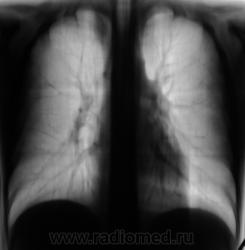

Пациента прислали "из туба" для томографии верхушек.

Получили такие картинки. Ваше мнение уважаемые коллеги?

Процесс не в легком, это деформация заднего отрезка 2 ребра справа или мне кажется ?

Спасибо за высказанное мнение коллега. Мы, также расценили, как деформацию и некоторую "гипертрофию" заднего фрагмента 2 ребра.